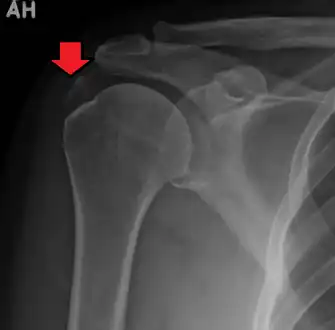

| A plain X ray of the shoulder showing calcific tendinitis | |

Calcific tendinitis is typically diagnosed by physical examination and X-ray imaging.[1] During the formative phase, X-ray images typically reveal calcium deposits with uniform density and a clear margin.[1] In the more painful resorptive phase, deposits instead appear cloudy and with unclear margins.[1] By arthroscopy, formative stage deposits appear crystalline and chalk-like, while resorptive stage deposits appear smooth resembling toothpaste.[1] Ultrasound is also used to locate and assess calcium deposits. In the formative stage, deposits are hyperechoic and arc-shaped; in the resorptive stage deposits are less echogenic and appear fragmented.[1][3]

An x-ray showing calcific deposits in the area of the tendons of the rotator cuff muscles